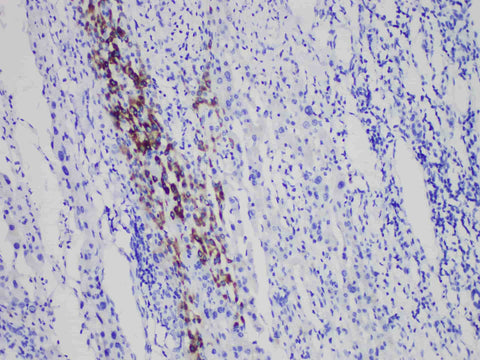

HbsAg Monoclonal Antibody

Applications IHC-P

Tissue Specificity Liver cancer

HBsAg is the surface antigen of hepatitis B virus, and its positive expression is mostly found in hepatocytes of hepatitis B and cirrhosis and a few hepatocellular carcinoma, which is often used to mark hepatocytes or tumor cells of such diseases.